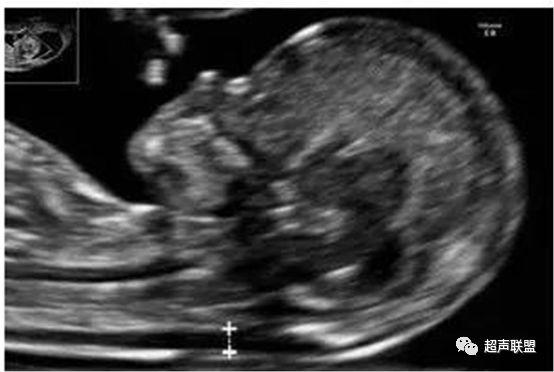

胎儿nt测量

nt测量的标准切面(宝宝的大头照)